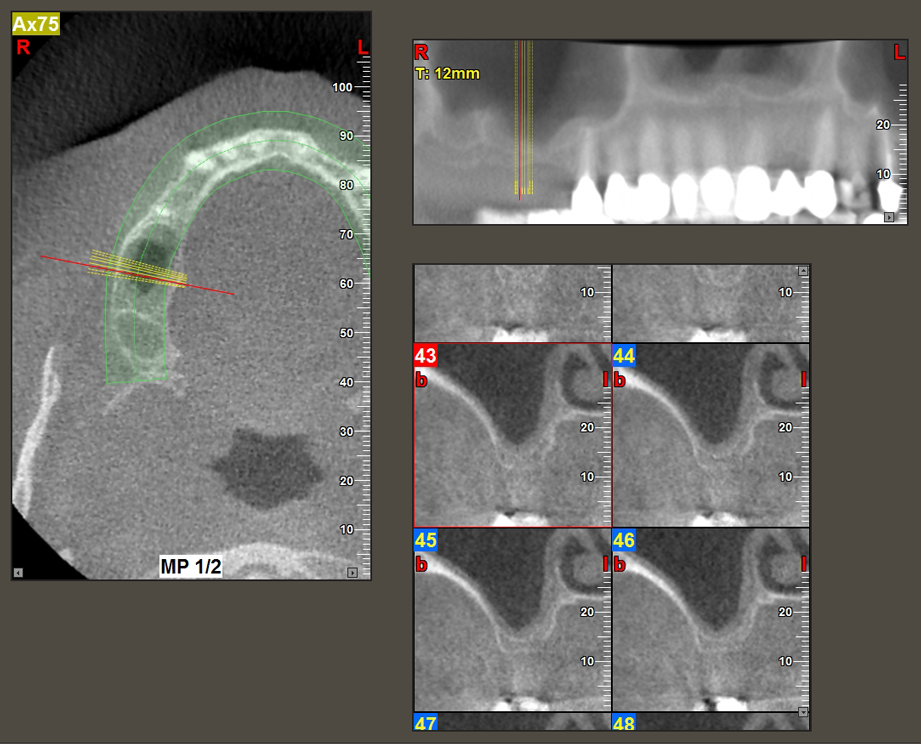

A 49-year-old female patient, a non-smoker and with nothing remarkable in her general medical history, was referred to our oral surgery practice for surgical extraction of tooth 16 and subsequent implantation. After the extraction, the patient experienced mild sinusitis trouble with the resultthat we initially waited six months before carrying out the measure. The residual bone height at the planned implant position measured 3-4 mm (Fig. 1 and 2).

Following atraumatic preparation of the mucoperiosteal flap, the implant position was marked with the I1 instrument and the site prepared – until initial resistance was felt. Piezosurgical instruments were used in an up and down movement without any pressure being exerted. The piezoelectric vibration produced the desired and efficient cavitation.

The I2A instrument (diameter 2.0 mm) was then used to perforate the sinus floor intermittently and on the smallest scale possible. This special piezosurgical method ensures that the Schneiderian membrane is not damaged. When the Z25P was used, the membrane was already lifted slightly by the coolant supplied via the instrument tip (Fig. 3). The coolant quantity was just 50% in order to avoid high pressure in the implant bed.

Implant bed preparation and augmentation

Following an intermediate check (Fig. 4) a further preparation step was performed (Fig. 5). Afterwards, the hydraulic Z35P instrument was used to lift the membrane to the desired position (Fig. 6 and 7). This was followed by further piezosurgical preparation of the implant bed, concluded with a rotary bur and shoulder milling cutter up to the implant diameter of 4.8 mm. Before the implant was inserted, the augmentation material (particle size approx. 0.8-1.6 mm) was introduced underneath the Schneiderian membrane (Fig. 8).